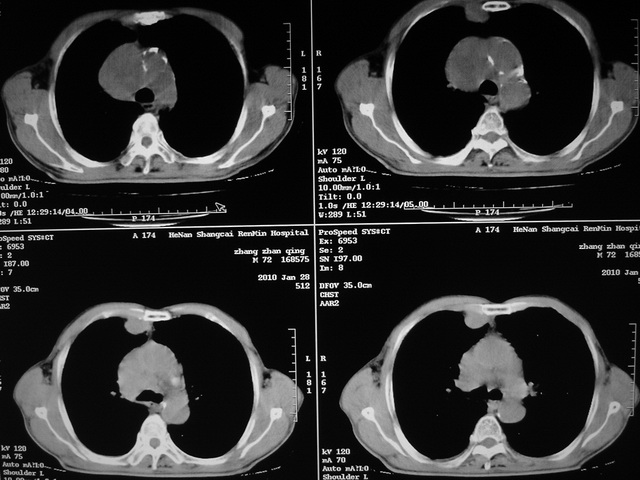

xx m 72岁农民 右侧胸痛6月余,咳嗽,无发热、咯血等

右下周围型肺癌,并右肺门、纵膈淋巴结、内乳淋巴结转移,右胸膜转移累及前胸壁。鉴别:脓肿、tb、淋巴瘤。病理类型可能为大细胞型。

这个病人有点复杂了,上纵隔像是占位,右肺下叶见壁光整厚壁空洞加液平,像是肺脓肿,中叶病灶牵涉到胸膜及胸壁,形态看像是炎性病变,总之不能除外恶性病变,还是穿刺或增强后再说。

右下周围型肺癌。偏心空洞形成伴感染。

支持2搂,考虑右肺下叶周围性肺癌伴肺门及纵膈淋巴结转移!右侧前纵膈病灶,还是一元论考虑为胸壁或胸膜转移瘤。